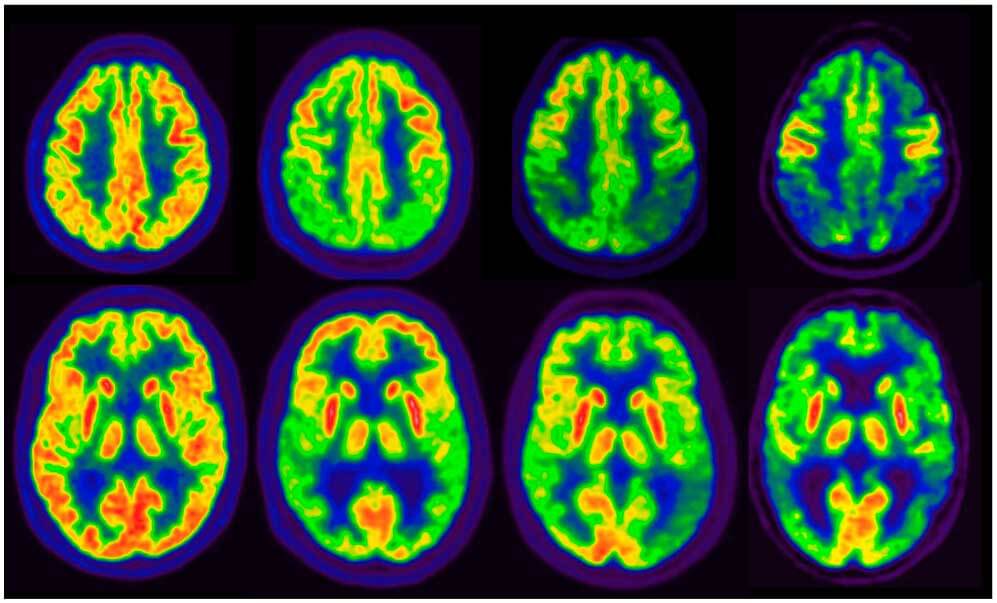

La tomografía por emisión de positrones de amiloide produce un incremento del tratamiento de pacientes con deterioro cognitivo leve o demencia

JAMA, 2 de abril 2019el manejo del paciente 90 días después de la PET amiloide (en comparación con el plan pre-PET) cambio en el 60,2% de los pacientes con deterioro cognitivo leve y el 63,5% de los pacientes con demencia.